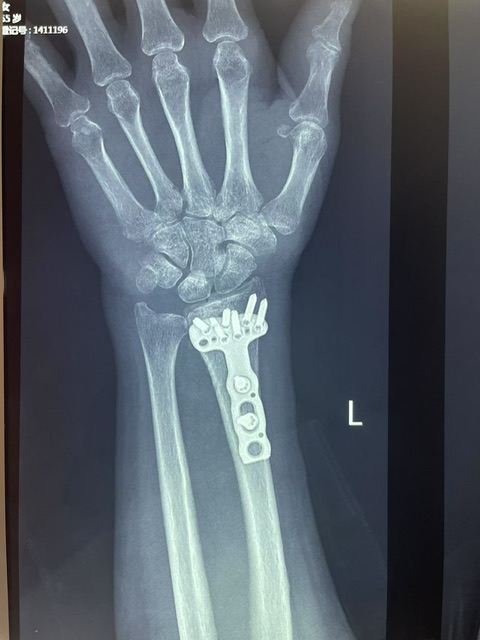

3. 误区3:“摔倒后没流血就没事”——桡骨骨折多为闭合性骨折(不流血),但会出现肿胀、疼痛、畸形,切勿忽视,若不及时治疗,会导致骨折愈合不良,影响手腕功能。